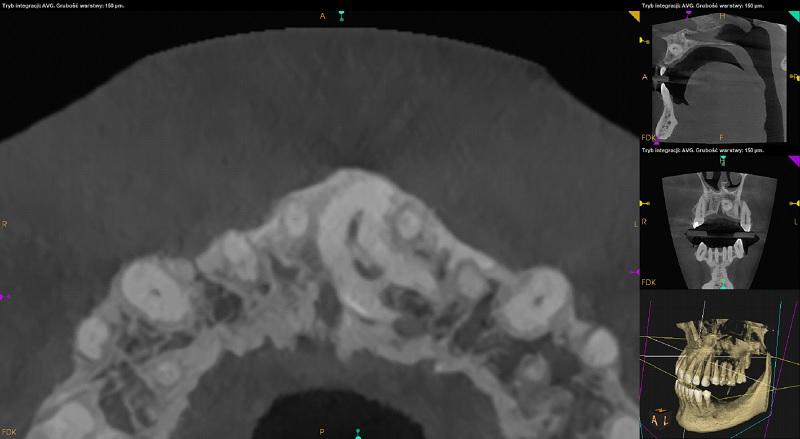

Pacjent: wiek 43 l.

Badanie z dnia: 30.09.2021

Badanie wykonano na aparacie: Kodak CS 9600

Parametry techniczne badania: 120kV, 8mA, 20s, 1457mGy*cm²

Szczęka.

Pomiędzy zębami 11 i 21 widoczny zatrzymany mesiodens. Położony poziomo, koroną skierowany w stronę podniebienną. Korzeń zagięty, przylega do kanału przysiecznego. Resorpcja korzeni zębów sąsiednich niewidoczna. Radiologiczne przejaśnienie w koronie zęba zatrzymanego może odpowiadać resorpcji.

Po stronie podniebiennej wierzchołków korzeni zębów 22-23 zatrzymany ząb dodatkowy. Położony pionowo skośnie, koroną skierowany w stronę dystalną. Korzeń przylega do dna przewodu nosowego dolnego lewego. Radiologiczne przejaśnienie w koronie zęba zatrzymanego może odpowiadać resorpcji.